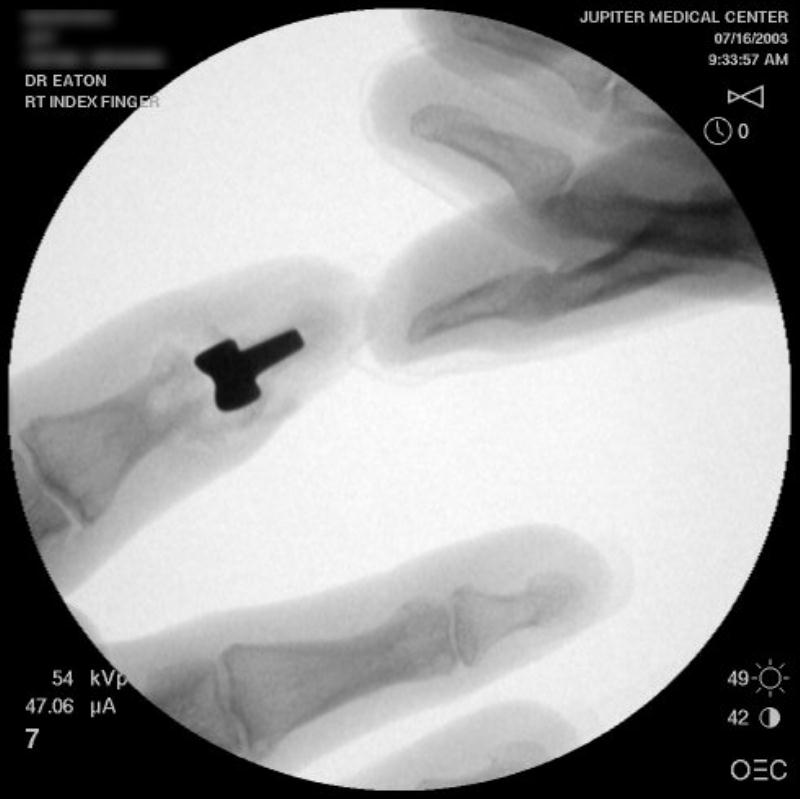

Intraoperative fluoroscopy.

The trial implant sizer shows the true size of the implant. The final implant has a radiolucent coating  which makes it appear smaller than it is on Xray.

Final implant radiographs.